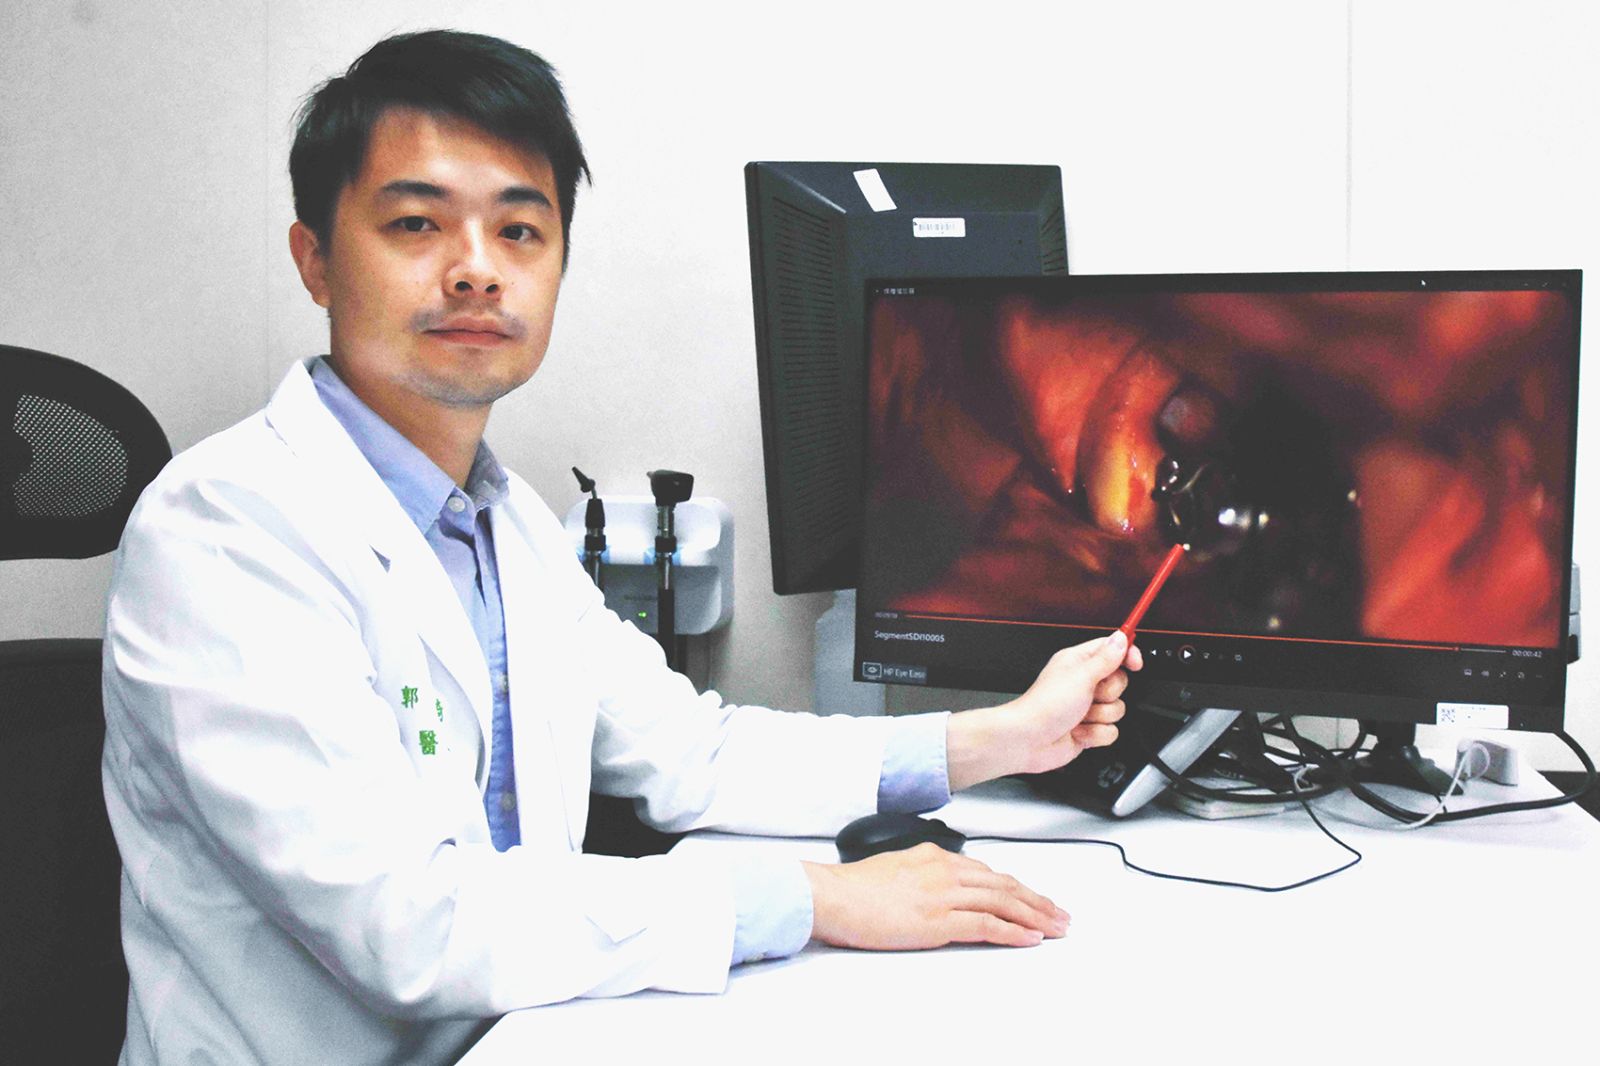

▲郭明錡醫師表示,隨著科技的發達,現在有用經皮穿刺置放導管到顱內,置放線圈和支架來治癒動脈瘤。

(彰基醫院提供)

郭明錡說,顱內動脈瘤的高致死率讓其成為一大隱患。家族病史、吸煙、三高、壓力和大量飲酒等都是致病風險因子,約1-2%的國人可能患有此病而不自知。某些遺傳性疾病如神經纖維瘤第一型、遺傳性纖維組織病變和遺傳性多囊腎病變,也可能引發顱內動脈瘤,但多數病例並無家族史,發病年齡多在40-60歲之間。